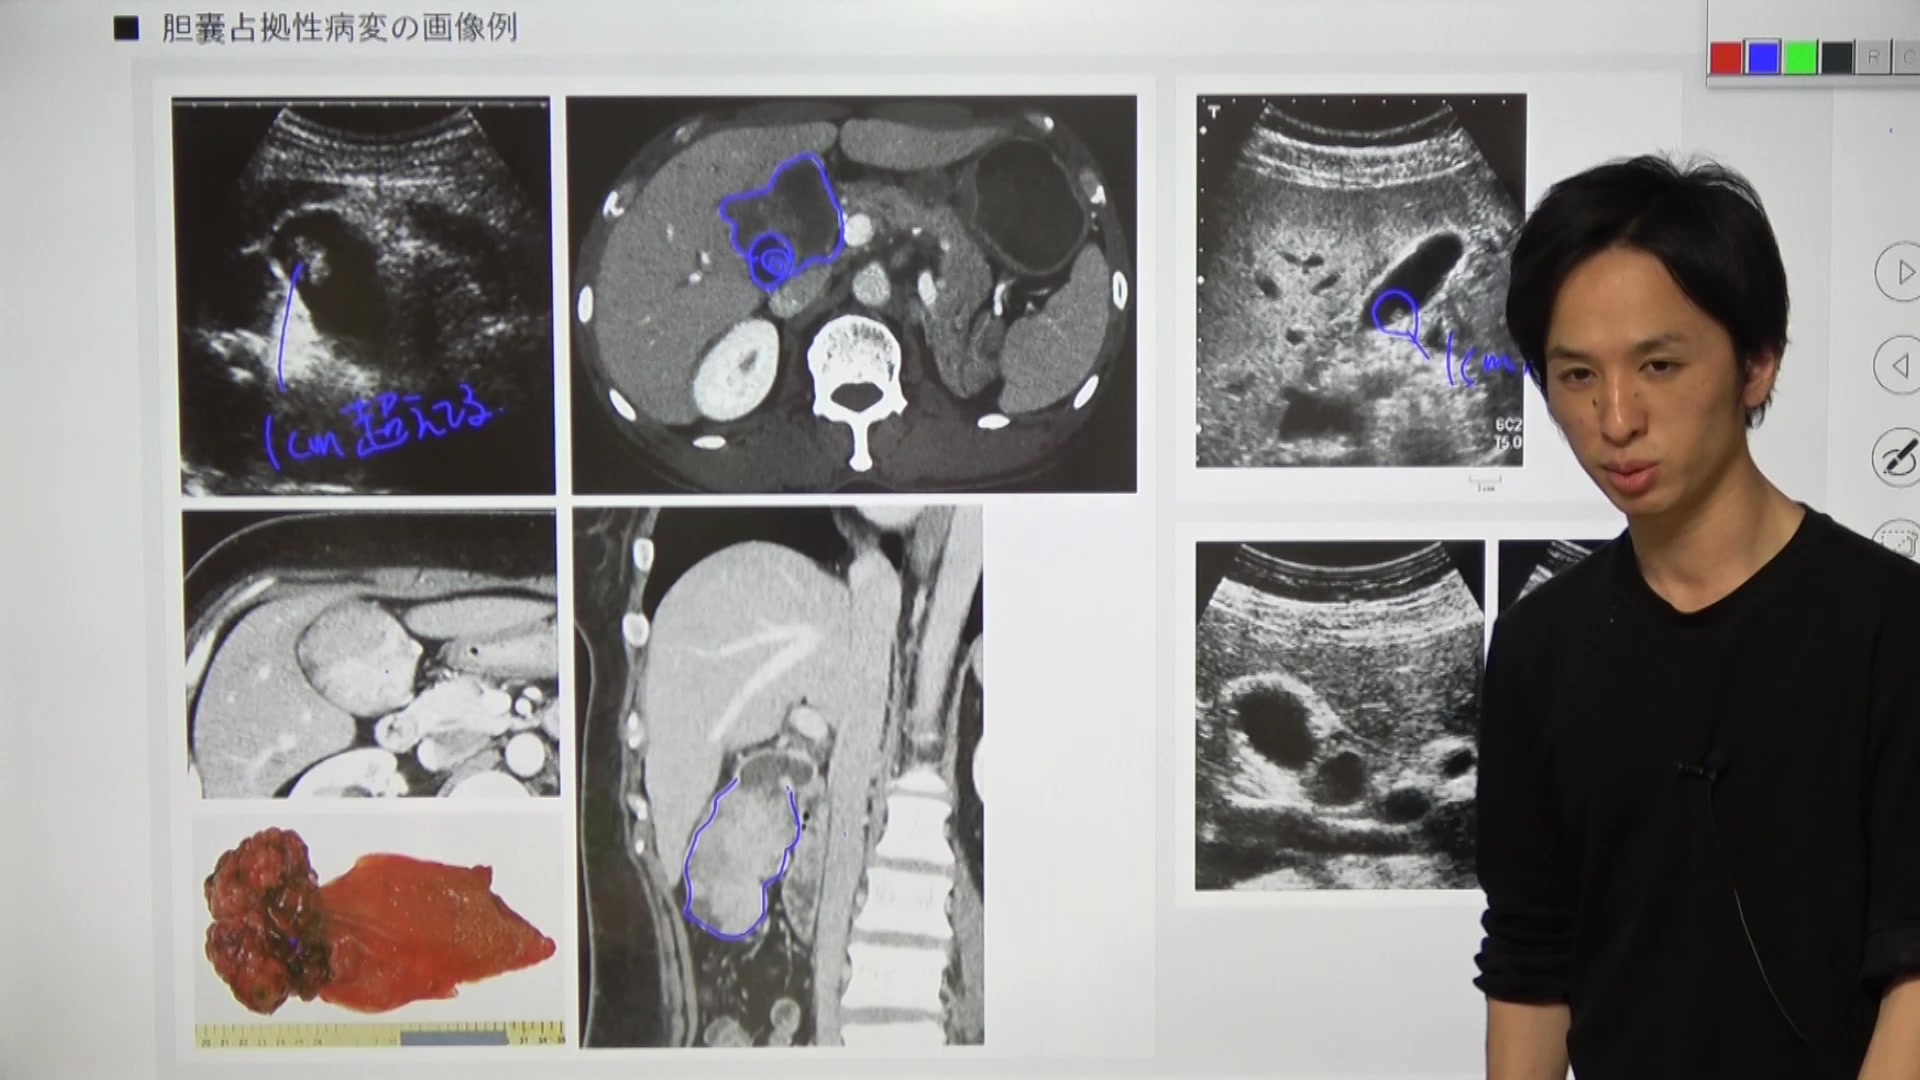

胆囊癌・ポリープ・腺筋腫症